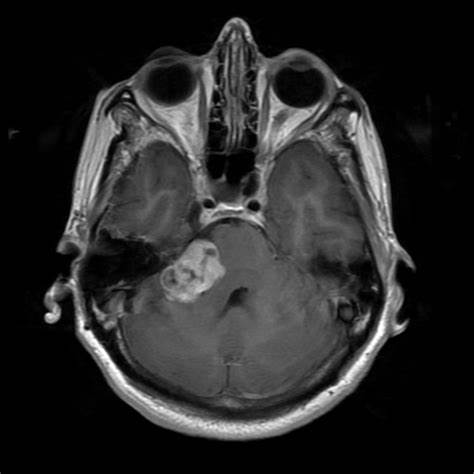

听神经瘤约占颅内肿瘤的7%。听力丧失、耳鸣、眩晕和不稳定是其早期症状。其他症状只出现在肿瘤长大后压迫大脑。早期诊断取决于MRI和听力学检查,包...

听神经瘤是什么? 大多数听神经瘤起源于前庭神经的上前庭。通过神经鞘瘤生长,内听道扩大,内听道逐渐生长,然后进入颅内。根据其生长特点,内听道...

据统计,小脑角肿瘤占全部颅内肿瘤的6-10%。桥小脑角(CPA)是指脑桥、延髓、小脑的交界处,位于后颅窝的前外侧,是由前内侧的桥脑外缘、外后方的岩...